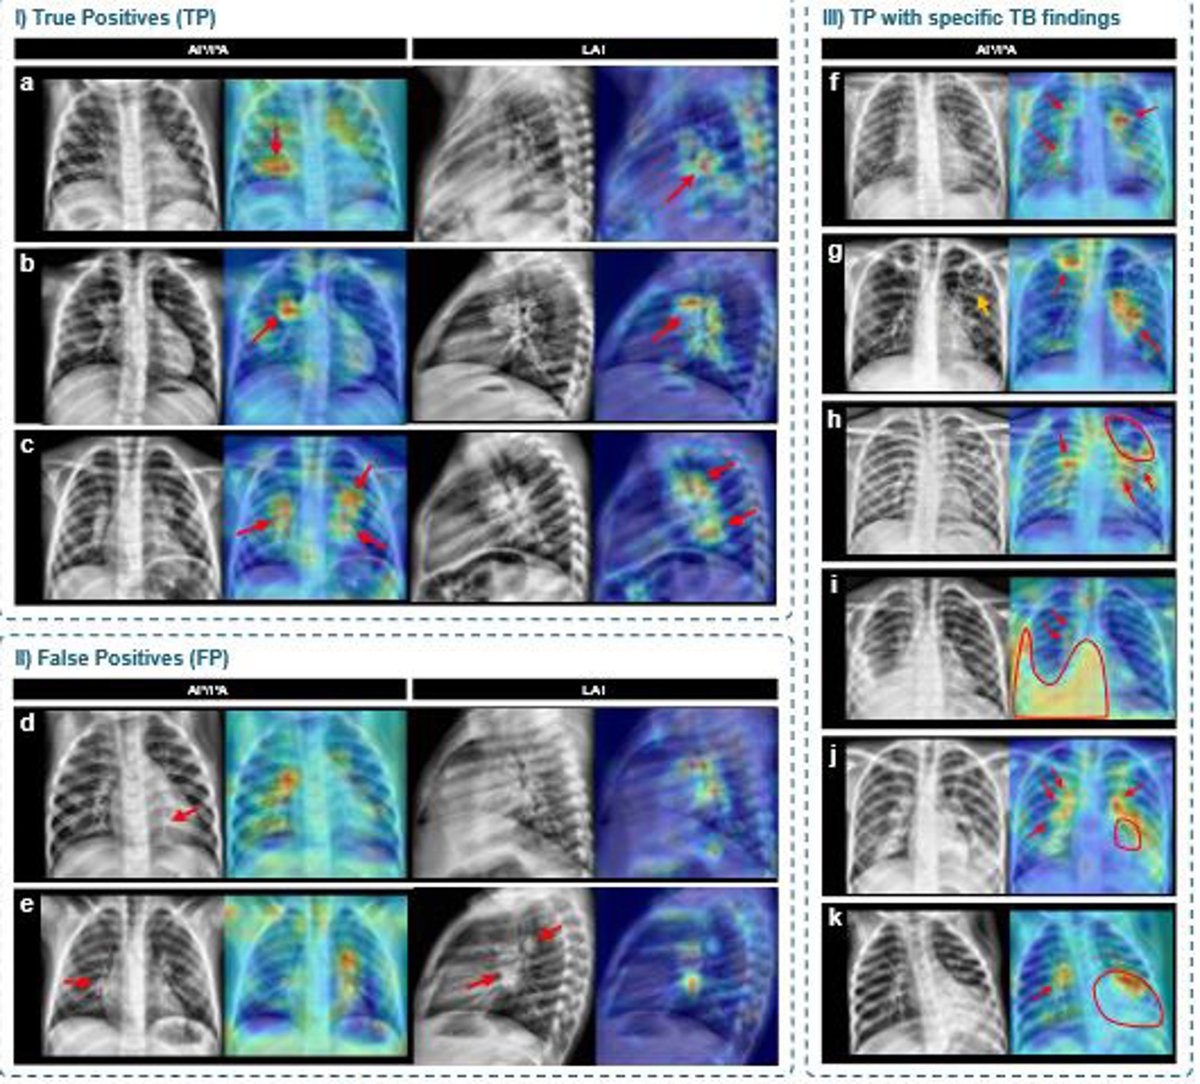

Mapas de activación generados mediante técnicas de explicabilidad que señalan las regiones de interés utilizadas por el modelo para tomar sus decisiones sobre las radiografías

Además de los resultados cuantitativos, el equipo incorporó técnicas de inteligencia artificial explicable que generan mapas visuales señalando las zonas de la radiografía que influyeron en cada decisión. Desde la UPC han subrayado que estas representaciones facilitan la revisión clínica de las predicciones y aumentan la confianza en el uso asistido por IA.